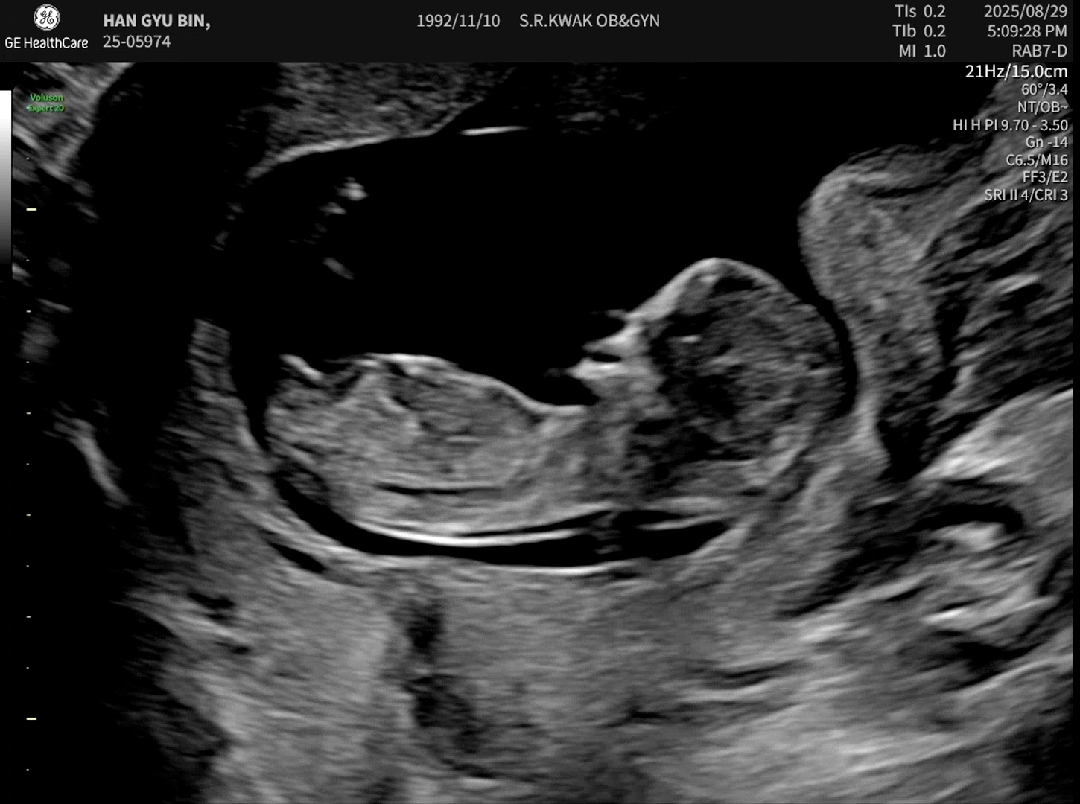

12주0일차! 드디어 손꼽아 기다리던 각도법 문의해볼수있게 됐네요 ㅎㅎㅎ🥹 근데 이 사진에 저기 보이는 돌출 부분으로 보는게 맞는걸까요..?